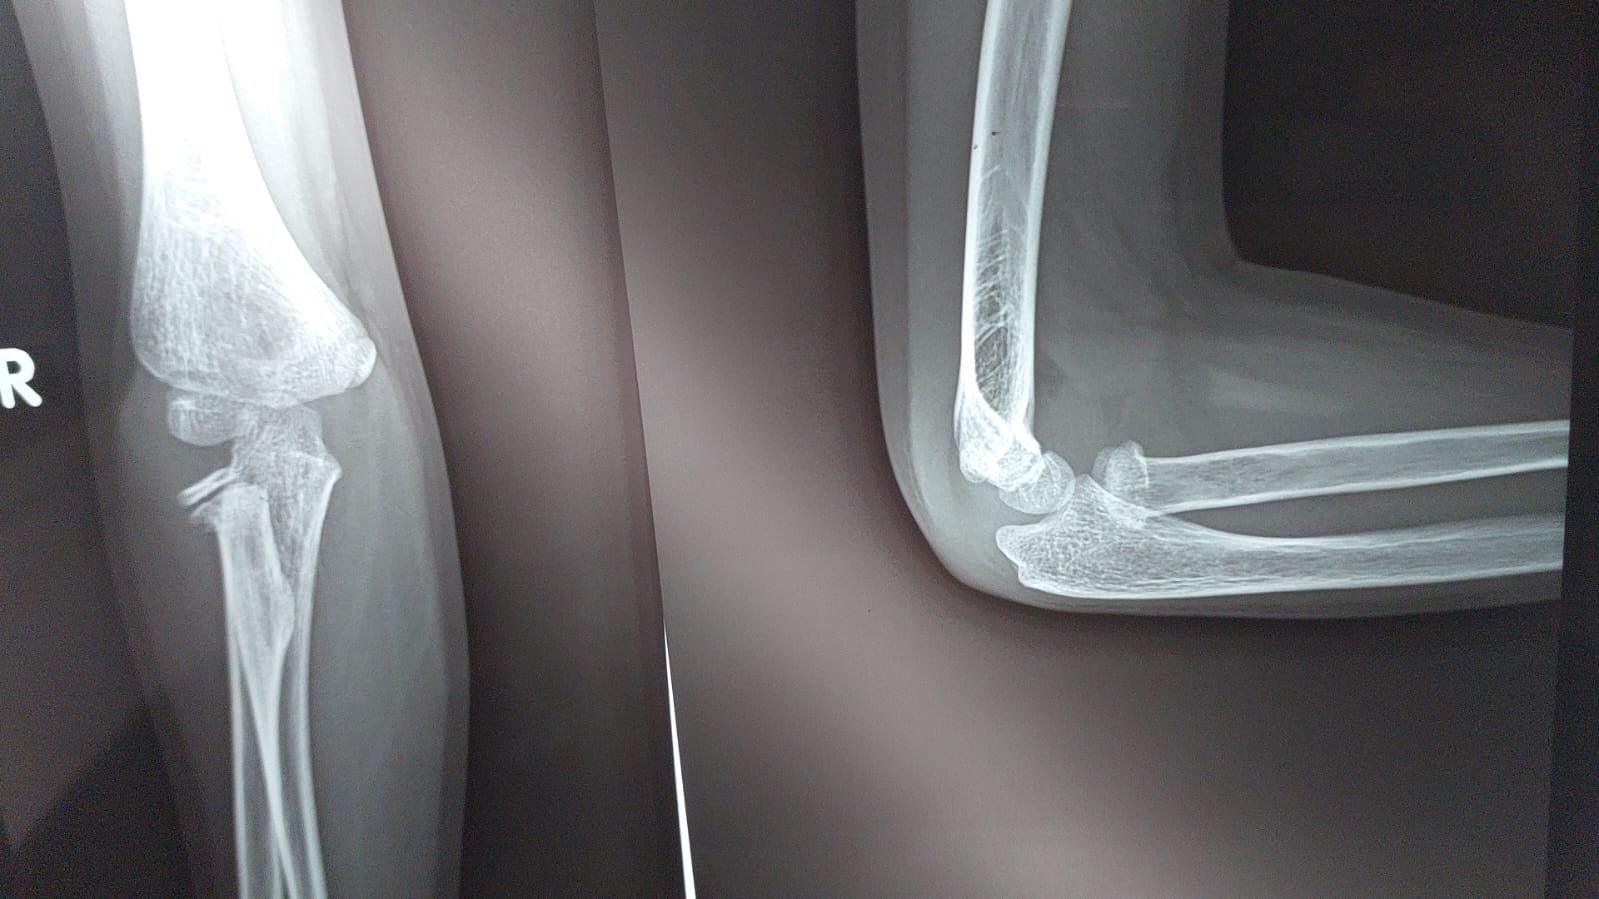

Radial Neck Fracture - Paediatric

This X-ray demonstrates a radial neck fracture in an 8-year-old child, visible on both AP and lateral views of the elbow. The fracture occurs at the junction of the radial head and radial shaft, with angulation...